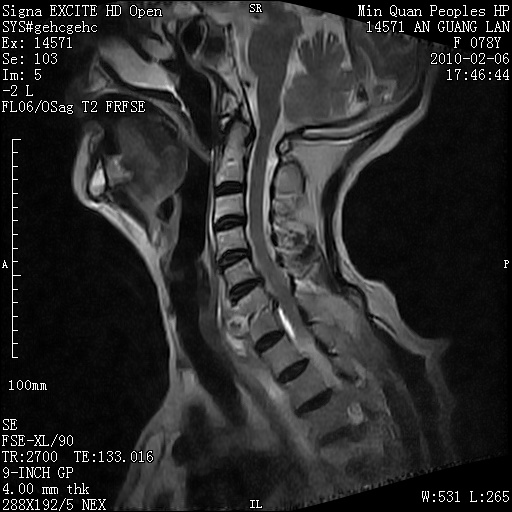

标题: MRI2763:C6、C7椎体病变性质?

f,78y,颈部与双上肢阵发性剧痛40余天。ct可见c6、c7椎体虫蚀样破坏,其间椎间隙变窄(没有图片资料可供上传)。

考虑椎体结核并椎旁脓肿。

考虑:c6/7椎体结核并椎旁脓肿形成,建议增强扫描。

单从影像表现此诊断不难,还应该结合临床资料排除其他